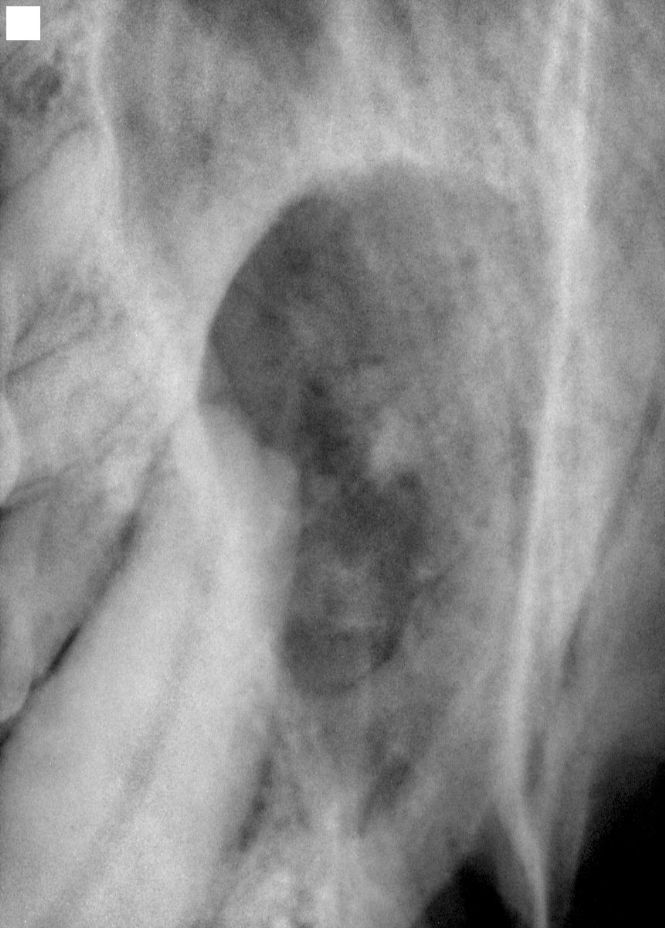

Dog Oral Neoplasia . Diagnosis and treatment of common canine oral tumours. Oral tumors are the fourth most common tumors seen in dogs, accounting for 6% of all canine tumors and up to 12% of tumors in cats. 1 oral tumors can originate from several sites in. In dogs, the three most common malignant oral tumors are malignant melanoma, squamous cell carcinoma, and fibrosarcoma. An oral tumor is an abnormal growth and unregulated replication of cells that occur within the mouth. There are various tissues within the oral cavity of animals that may. A dog’s mouth, similar to our own, is made up of several different cell types; Here’s everything you need to know about oral cancer in dogs, from the symptoms and treatment to life expectancy. Oral tumors are the 4th most common cancer formed in the dog. Are you worried that your dog might have mouth cancer? In cases of canine oral tumours, achieving a definitive diagnosis prior to treatment is essential as surgical. The most common oral tumors in dogs are malignant melanoma, squamous cell carcinoma, fibrosarcoma and acanthomatous ameloblastoma.